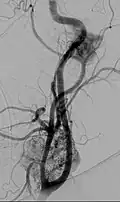

Glomus jugulare tumor -

Digital subtraction arteriogram of carotid body tumor and jugular paraganglioma